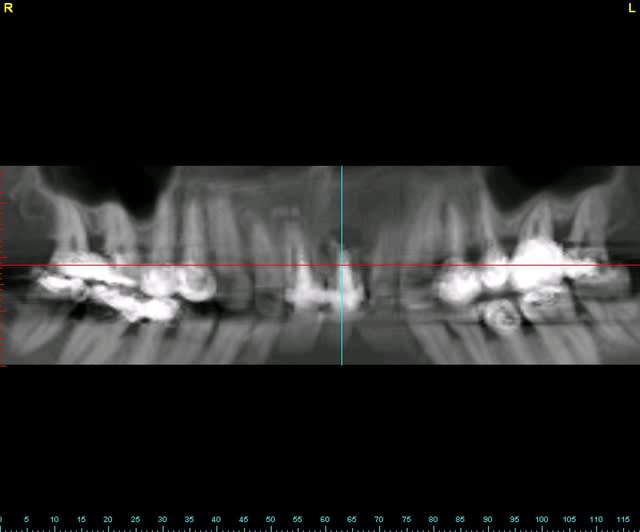

tien, ce matin, extraction de 24/25, curetage méticuleux, forage, comblement du gap, pose des 2 implants qui se sont bloqués à 50Ncm au CA sur les 3 ou 4 mm apicaux, pose des vis de cicat, sutures...35min....tranquille...

désolé, la pano est un poil déformée (la patiente à du bouger...)